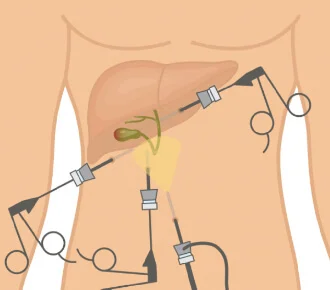

- Colecistectomia